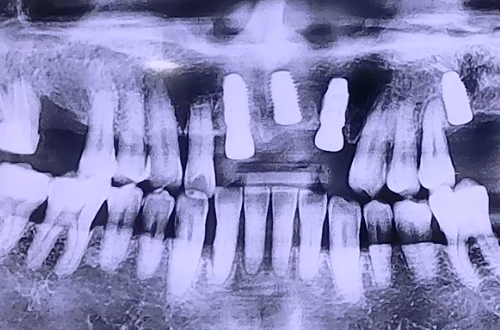

AFTER

3개의 앞니 임플란트를 진행하셨고, 빠진 앞니가 많이 보이는 것에 대해서

불편함을 말씀하셨기 때문에 임플란트가 단단히 굳는 기간 동안 불편하시지 않도록

임시 치아를 예쁘게 제작하여 수술 당일 바로 끼울 수 있도록 도와드렸습니다.

그 후 보철이 완성되어 예쁘고 튼튼한 앞니로 치료해 드렸고,

이후로도 지속적인 검진을 통해 문제 생기는 부분 없는지 체크해드릴 예정입니다.

환자분께서 매우 만족해하셔서 저희도 기쁜 치료였답니다! ^^